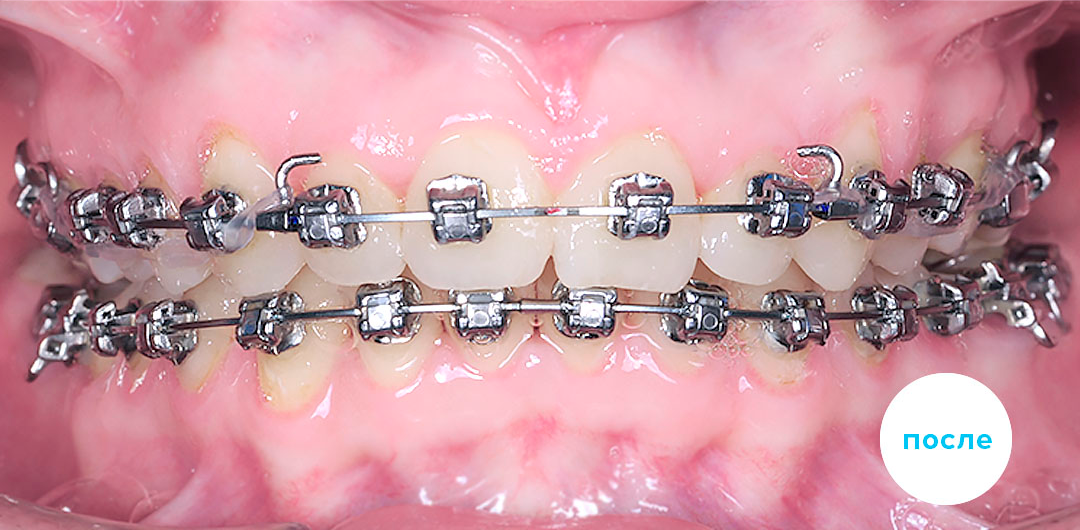

После

После

После